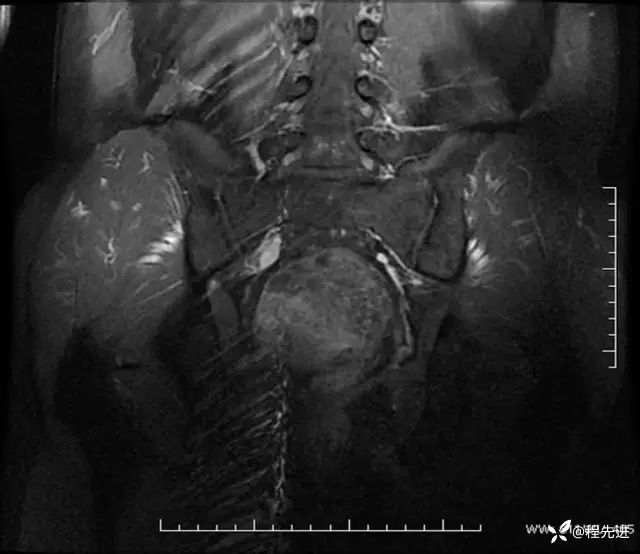

T2冠状位:

T1压脂增强冠状位: